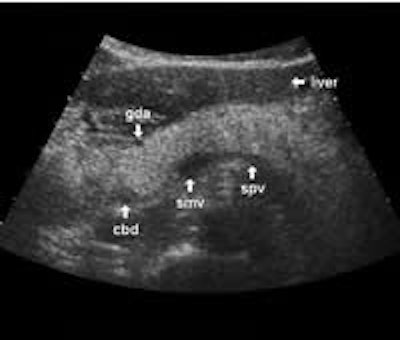

The following study describes anatomical landmarks in the ordinary pancreas of a thin patient:

Transverse planes in caudal direction:

The dorsal aspect of the head takes the shape of a hook surrounding the right side of the superior mesenteric vein; the sharp left-pointing tip of the hook behind the vein constitutes the uncinate process. The splenic vein runs from the left along the dorsal border of the tail and body to the superior mesenteric vein, where these veins join to form the portal vein behind the "neck" of the pancreas. The portal vein then leaves the pancreas to the right and slightly upwards and runs into the liver hilum.

The main bile duct runs from the liver hilum to the right of and above the portal vein into the right dorsal part of the pancreatic head, where it runs vertically into the duodenum. The pancreatic duct typically runs along the body and tail to join the common bile duct near the duodenum. The gastroduodenal artery is sometimes seen in its position along the front margin of the pancreatic head, where it runs in a nearly parallel direction to the common bile duct. Like the common bile duct and pancreatic duct, however, the gastroduodenal artery is not always clearly seen due to its small diameter. The duodenum covers the right and bottom margins of the pancreatic head.